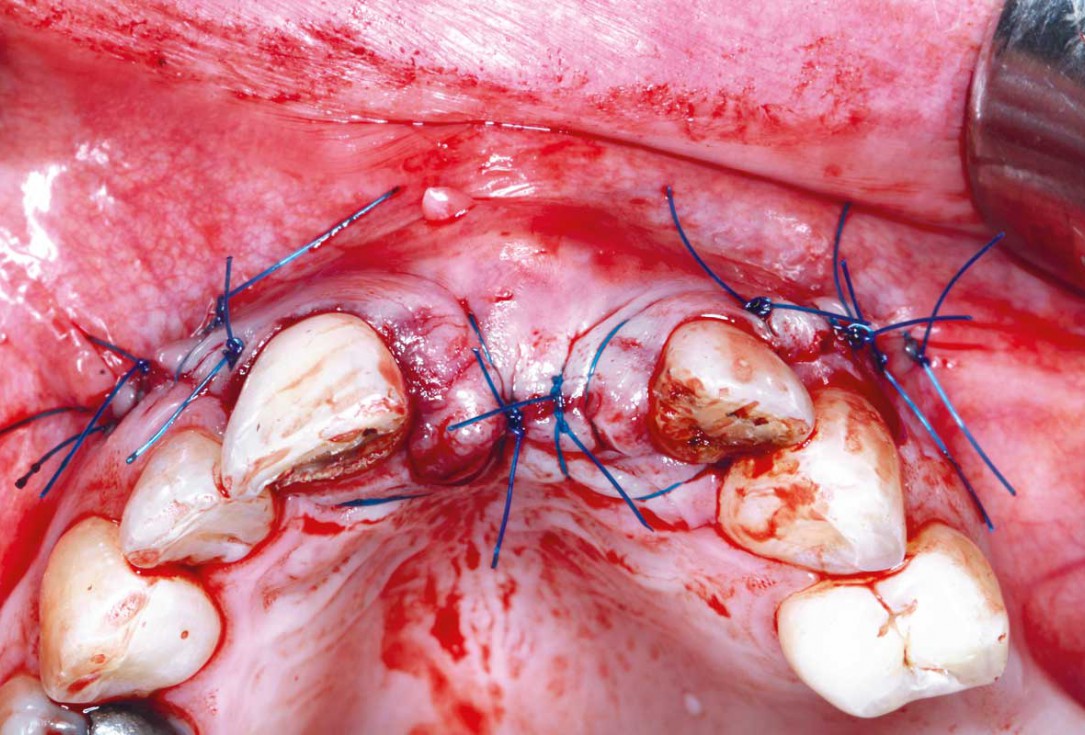

15/35 - Flap closure using 5/0 monofilaments Prolene suturesBlock grafting in the aesthetic zone with maxgraft®, Jason® membrane and cerabone® - Dres. H. Maghaireh and V. Ivancheva

16/35 - Flap closure using 5/0 monofilaments Prolene suturesBlock grafting in the aesthetic zone with maxgraft®, Jason® membrane and cerabone® - Dres. H. Maghaireh and V. Ivancheva